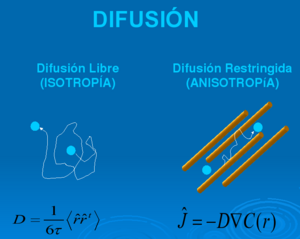

- 12.6 Molecular Diffusion in MRI: Technical Application of Fiber Tracking